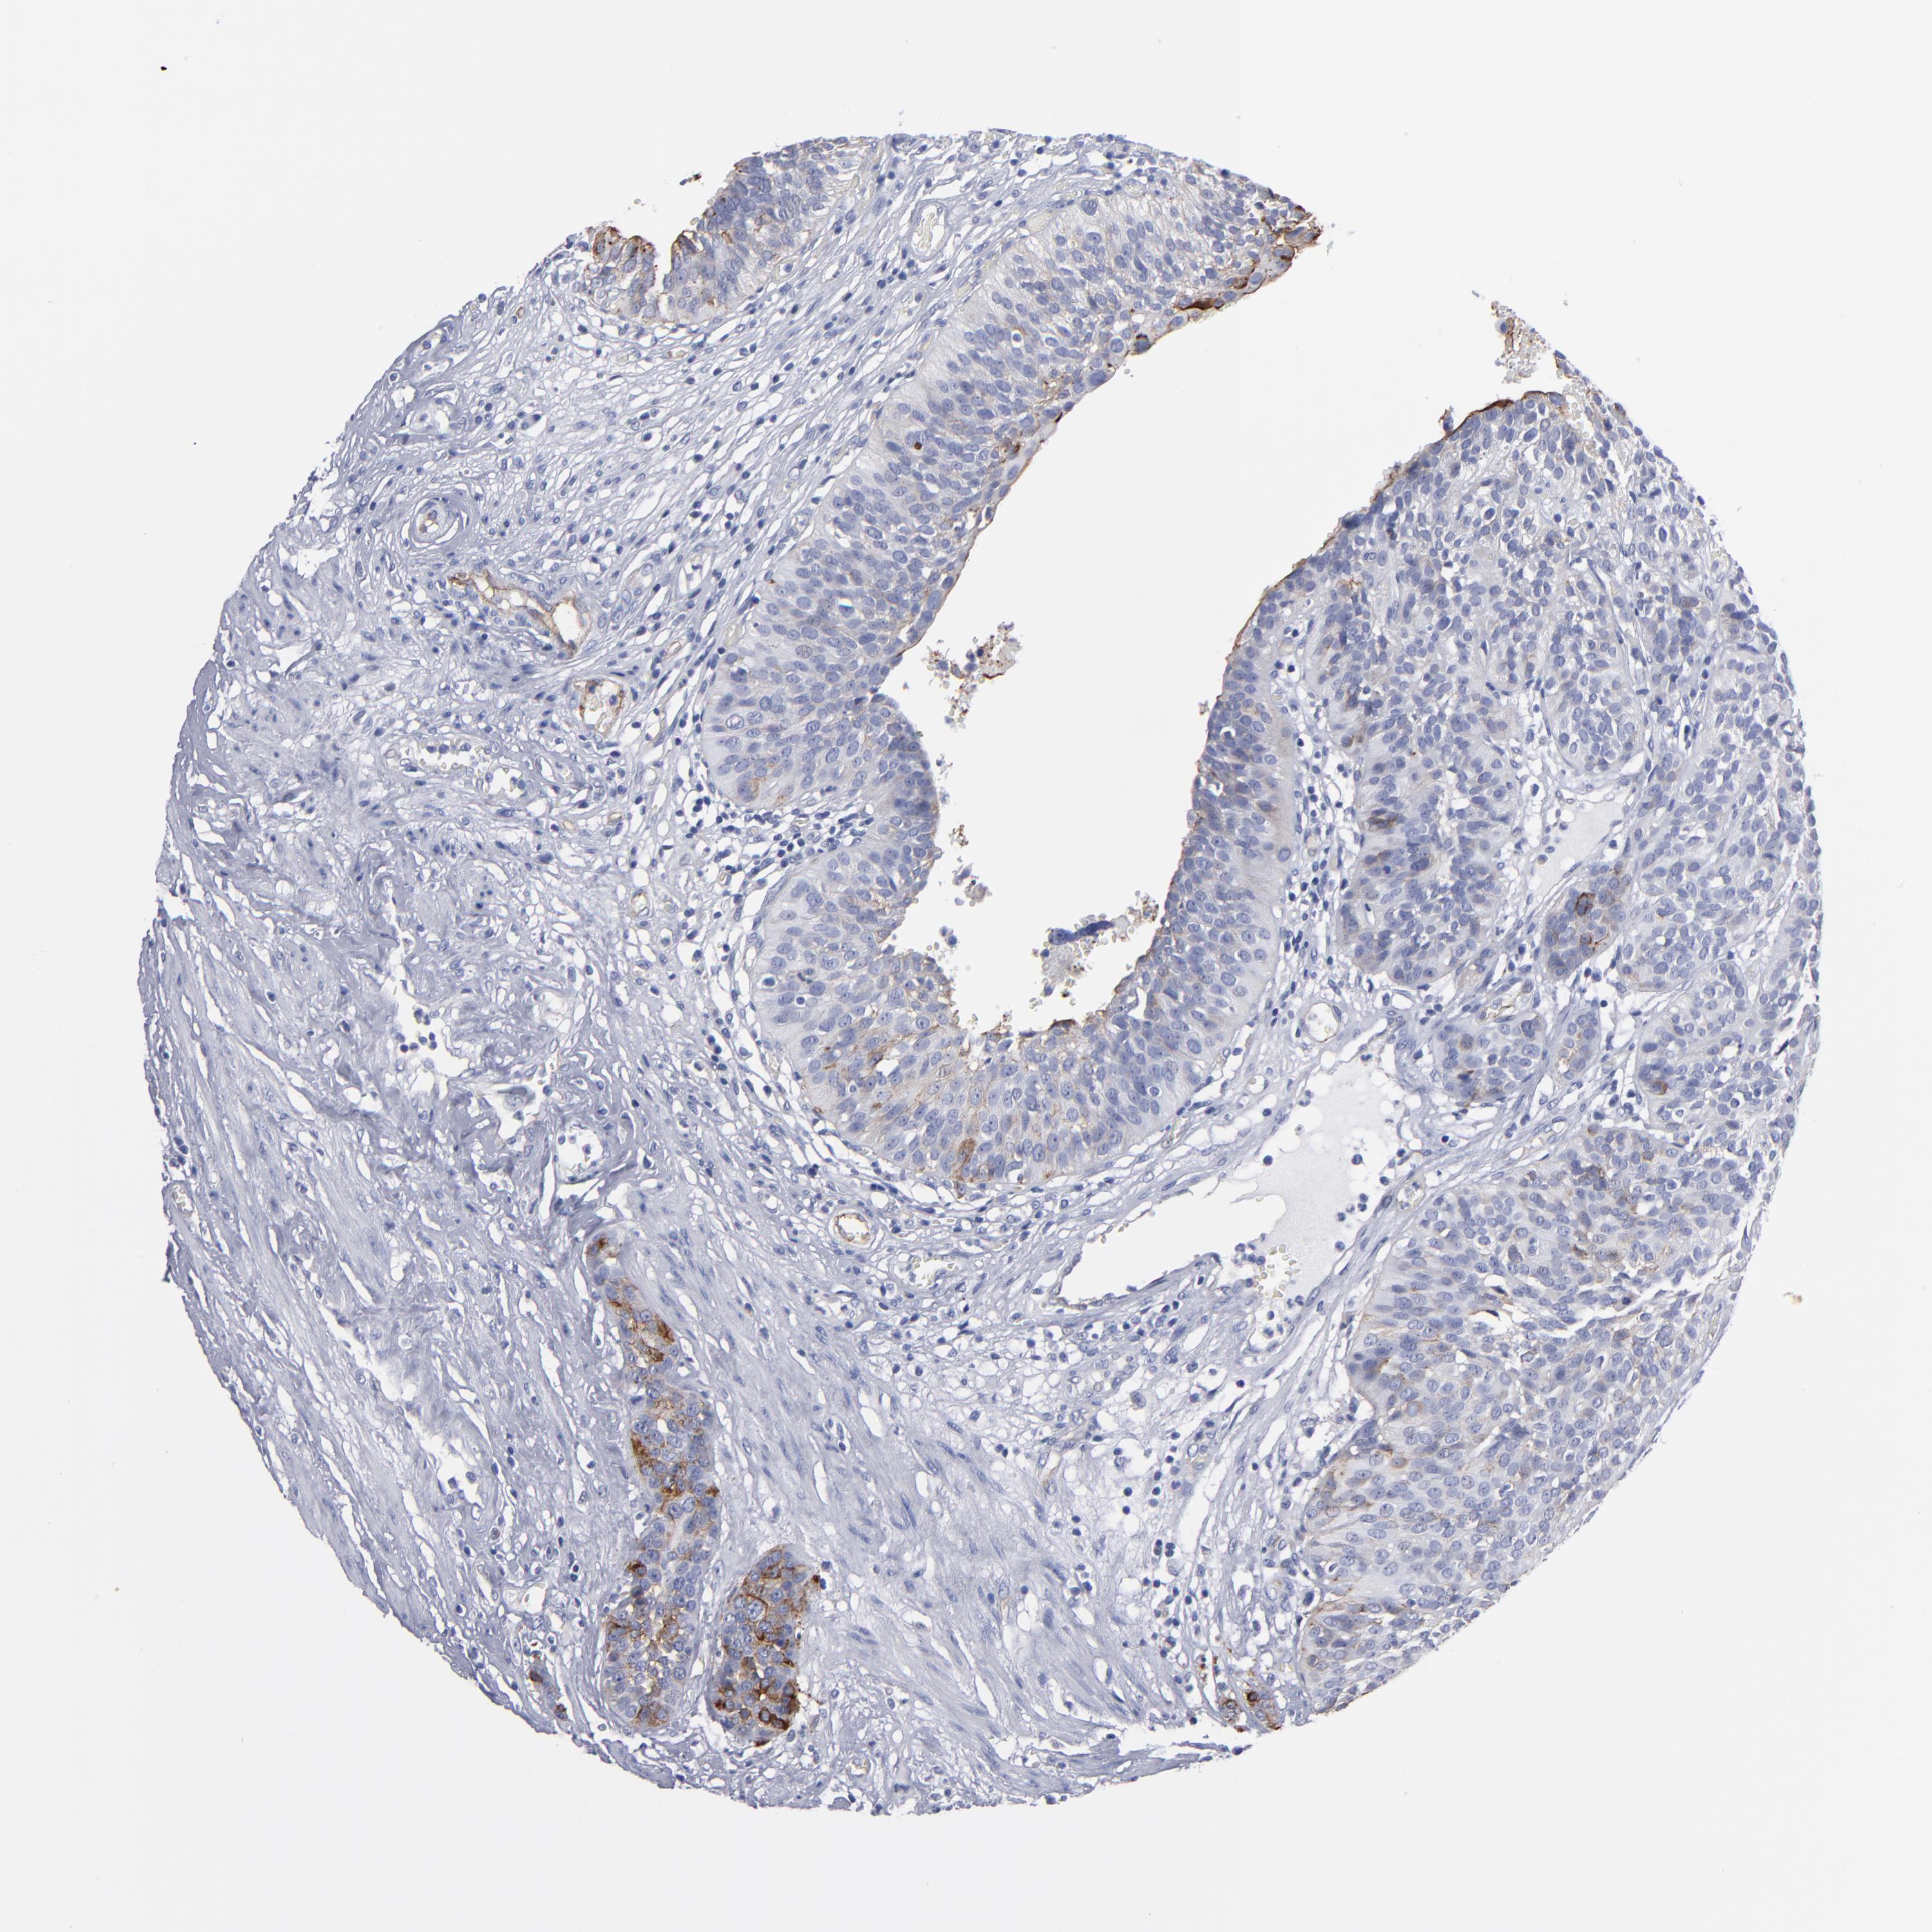

UROTHELIAL CANCER - Protein expressioni

A mouse-over function shows sample information and annotation data. Click on an image to view it in a full screen mode. Samples can be filtered based on level of antibody staining by selecting one or several of the following categories: high, medium, low and not detected. The assay and annotation is described here.

Note that samples used for immunohistochemistry by the Human Protein Atlas do not correspond to samples in the TCGA dataset.

Antibody stainingi

Antibody staining in the annotated cell types in the current human tissue is reported as not detected, low, medium, or high, based on conventional immunohistochemistry profiling in selected tissues. This score is based on the combination of the staining intensity and fraction of stained cells.

Each image is clickable and will lead to virtual microscopy that enables deeper exploration of all samples and also displays staining intensity scores, fraction scores and subcellular localization as well as patient and tissue information for each sample.

Antibody HPA002823

Antibody CAB002760

Staining

High

Medium

Low

Not detected

Intensity

Strong

Moderate

Weak

Negative

Quantity

>75%

75%-25%

<25%

None

Location

Nuclear

Cytoplasmic/membranous

Cytoplasmic/membranous,nuclear

Urothelial carcinoma, High grade

Urothelial carcinoma, Low grade

Adenocarcinoma, NOS